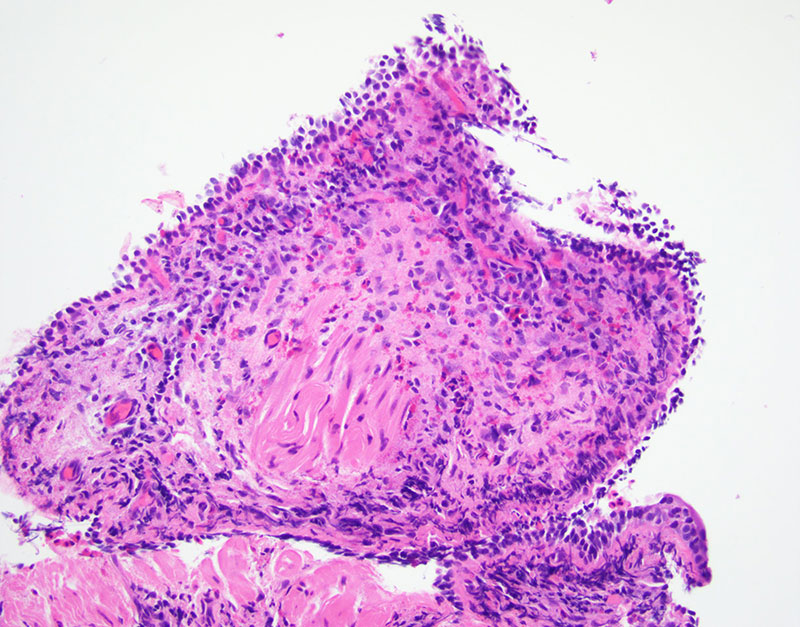

Transbronchial biopsy of the radiographic lesion was done and revealed fragments of bronchial wall and mucoid material with eosinophilic micro-abscesses (Figures 1-2). GMS and PAS stain were performed and highlight fungi with septate hyphae, morphologically suggestive of Aspergillus (Figure 3).